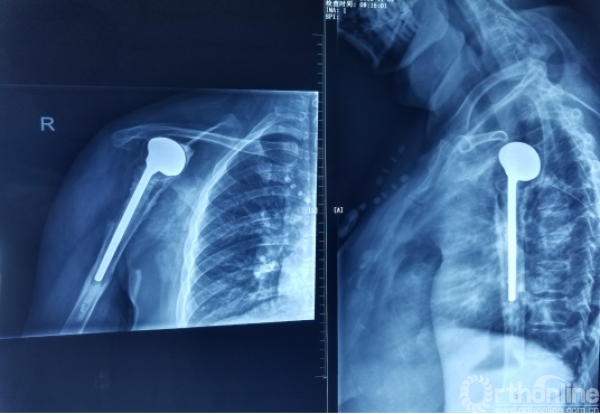

肩关节置换后11年松动合并感染

患者,女性,49岁,11年前因车祸致肱骨近端粉碎骨折(推测为NeerⅣ部分---骨折合并脱位),主管医师行急诊手术治疗(患者BMI>28);

患者术后未行及时拍片,2周后第一次拍片发现肱骨头脱位依然存在,出现纠纷;一月后,请外地专家行二次手术,半肩置换。

患者主诉:行右肩关节置换术后11年,发现腋窝红肿疼痛2月入院。

二次入院时X线检查